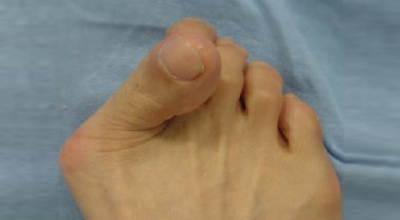

엄지발가락이 두번째 발가락 쪽으로 과도하게 휘고 엄지발가락과 관절을 이루는 중족골은 반대로 안쪽으로 치우치는 변형 되며 발가락이 발등 쪽으로 휘거나 회전(엄지발가락 축을 중점으로 내측으로 회전; 회내)하는 변형을 동반한 삼차원적인 변형을 말합니다.

무지외반증으로 인하여 변형이 심해지면 엄지발가락이 두 번째 발가락과 겹치거나 관절이 탈구되어 전반적으로 디디기 어려운 발이 되기도 합니다. 건강보험심사평가원의 무지외반증 환자 통계를 보면, 세대별로는 40대 이상에서 가장 많으며 성별로는 무지외반증 여성 환자 비율이 남성보다 월등하게 높았다고 합니다.

육안상으로 확연하게 엄지발가락 과 같은 변형 보이며 초기에는 굳은살도 관찰되고 약간의 통증도 있습니다. 엄지발가락 돌출 부위의 통증으로 이 부위가 신발에 자극을 받아 두꺼워지고 염증이 생겨 통증이 발생합니다. 휘어지지 않은 발바닥에 굳은살로 인해 정상 보행이 어렵고 심한 경우 통증으로 인하여 신발 착용은 물론 정상 보행도 어려워집니다. 연속적으로 증상이 악화되면 엄지발가락이 겹쳐지거나 탈구 될 수도 있습니다.